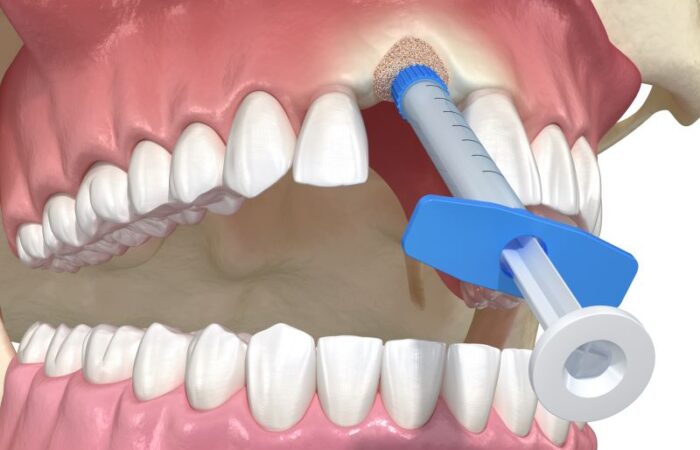

الطعوم العظمية السنية – الأنواع والبدائل

الطعوم العظمية السنية – الاستطبابات، الخصائص والآثار الجانبية